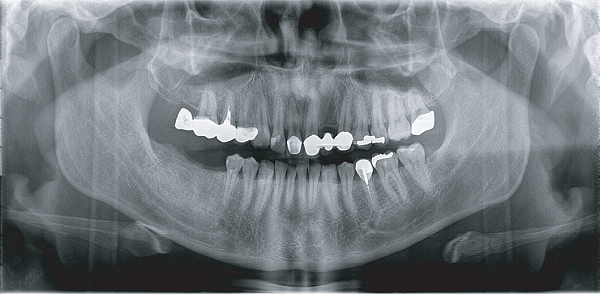

Apsaras 3D 口腔頜面錐形束計算機體層攝影設備

臨 床 圖 集